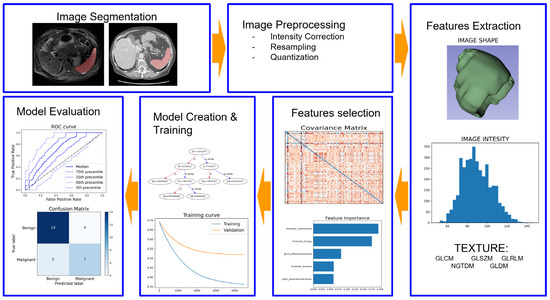

Radiomics Applications in Spleen Imaging: A Systematic Review and Methodological Quality Assessment

The spleen, often referred to as the “forgotten organ”, plays numerous important roles in various diseases. Recently, there has been an increased interest in the application of radiomics in different areas of medical imaging. This systematic review aims to assess the current state

The spleen, often referred to as the “forgotten organ”, plays numerous important roles in various diseases. Recently, there has been an increased interest in the application of radiomics in different areas of medical imaging. This systematic review aims to assess the current state of the art and evaluate the methodological quality of radiomics applications in spleen imaging. A systematic search was conducted on PubMed, Scopus, and Web of Science. All the studies were analyzed, and several characteristics, such as year of publication, research objectives, and number of patients, were collected. The methodological quality was evaluated using the radiomics quality score (RQS). Fourteen articles were ultimately included in this review. The majority of these articles were published in non-radiological journals (78%), utilized computed tomography (CT) for extracting radiomic features (71%), and involved not only the spleen but also other organs for feature extraction (71%). Overall, the included papers achieved an average RQS total score of 9.71 ± 6.37, corresponding to an RQS percentage of 27.77 ± 16.04. In conclusion, radiomics applications in spleen imaging demonstrate promising results in various clinical scenarios. However, despite all the included papers reporting positive outcomes, there is a lack of consistency in the methodological approaches employed.

Full article

Show Figures